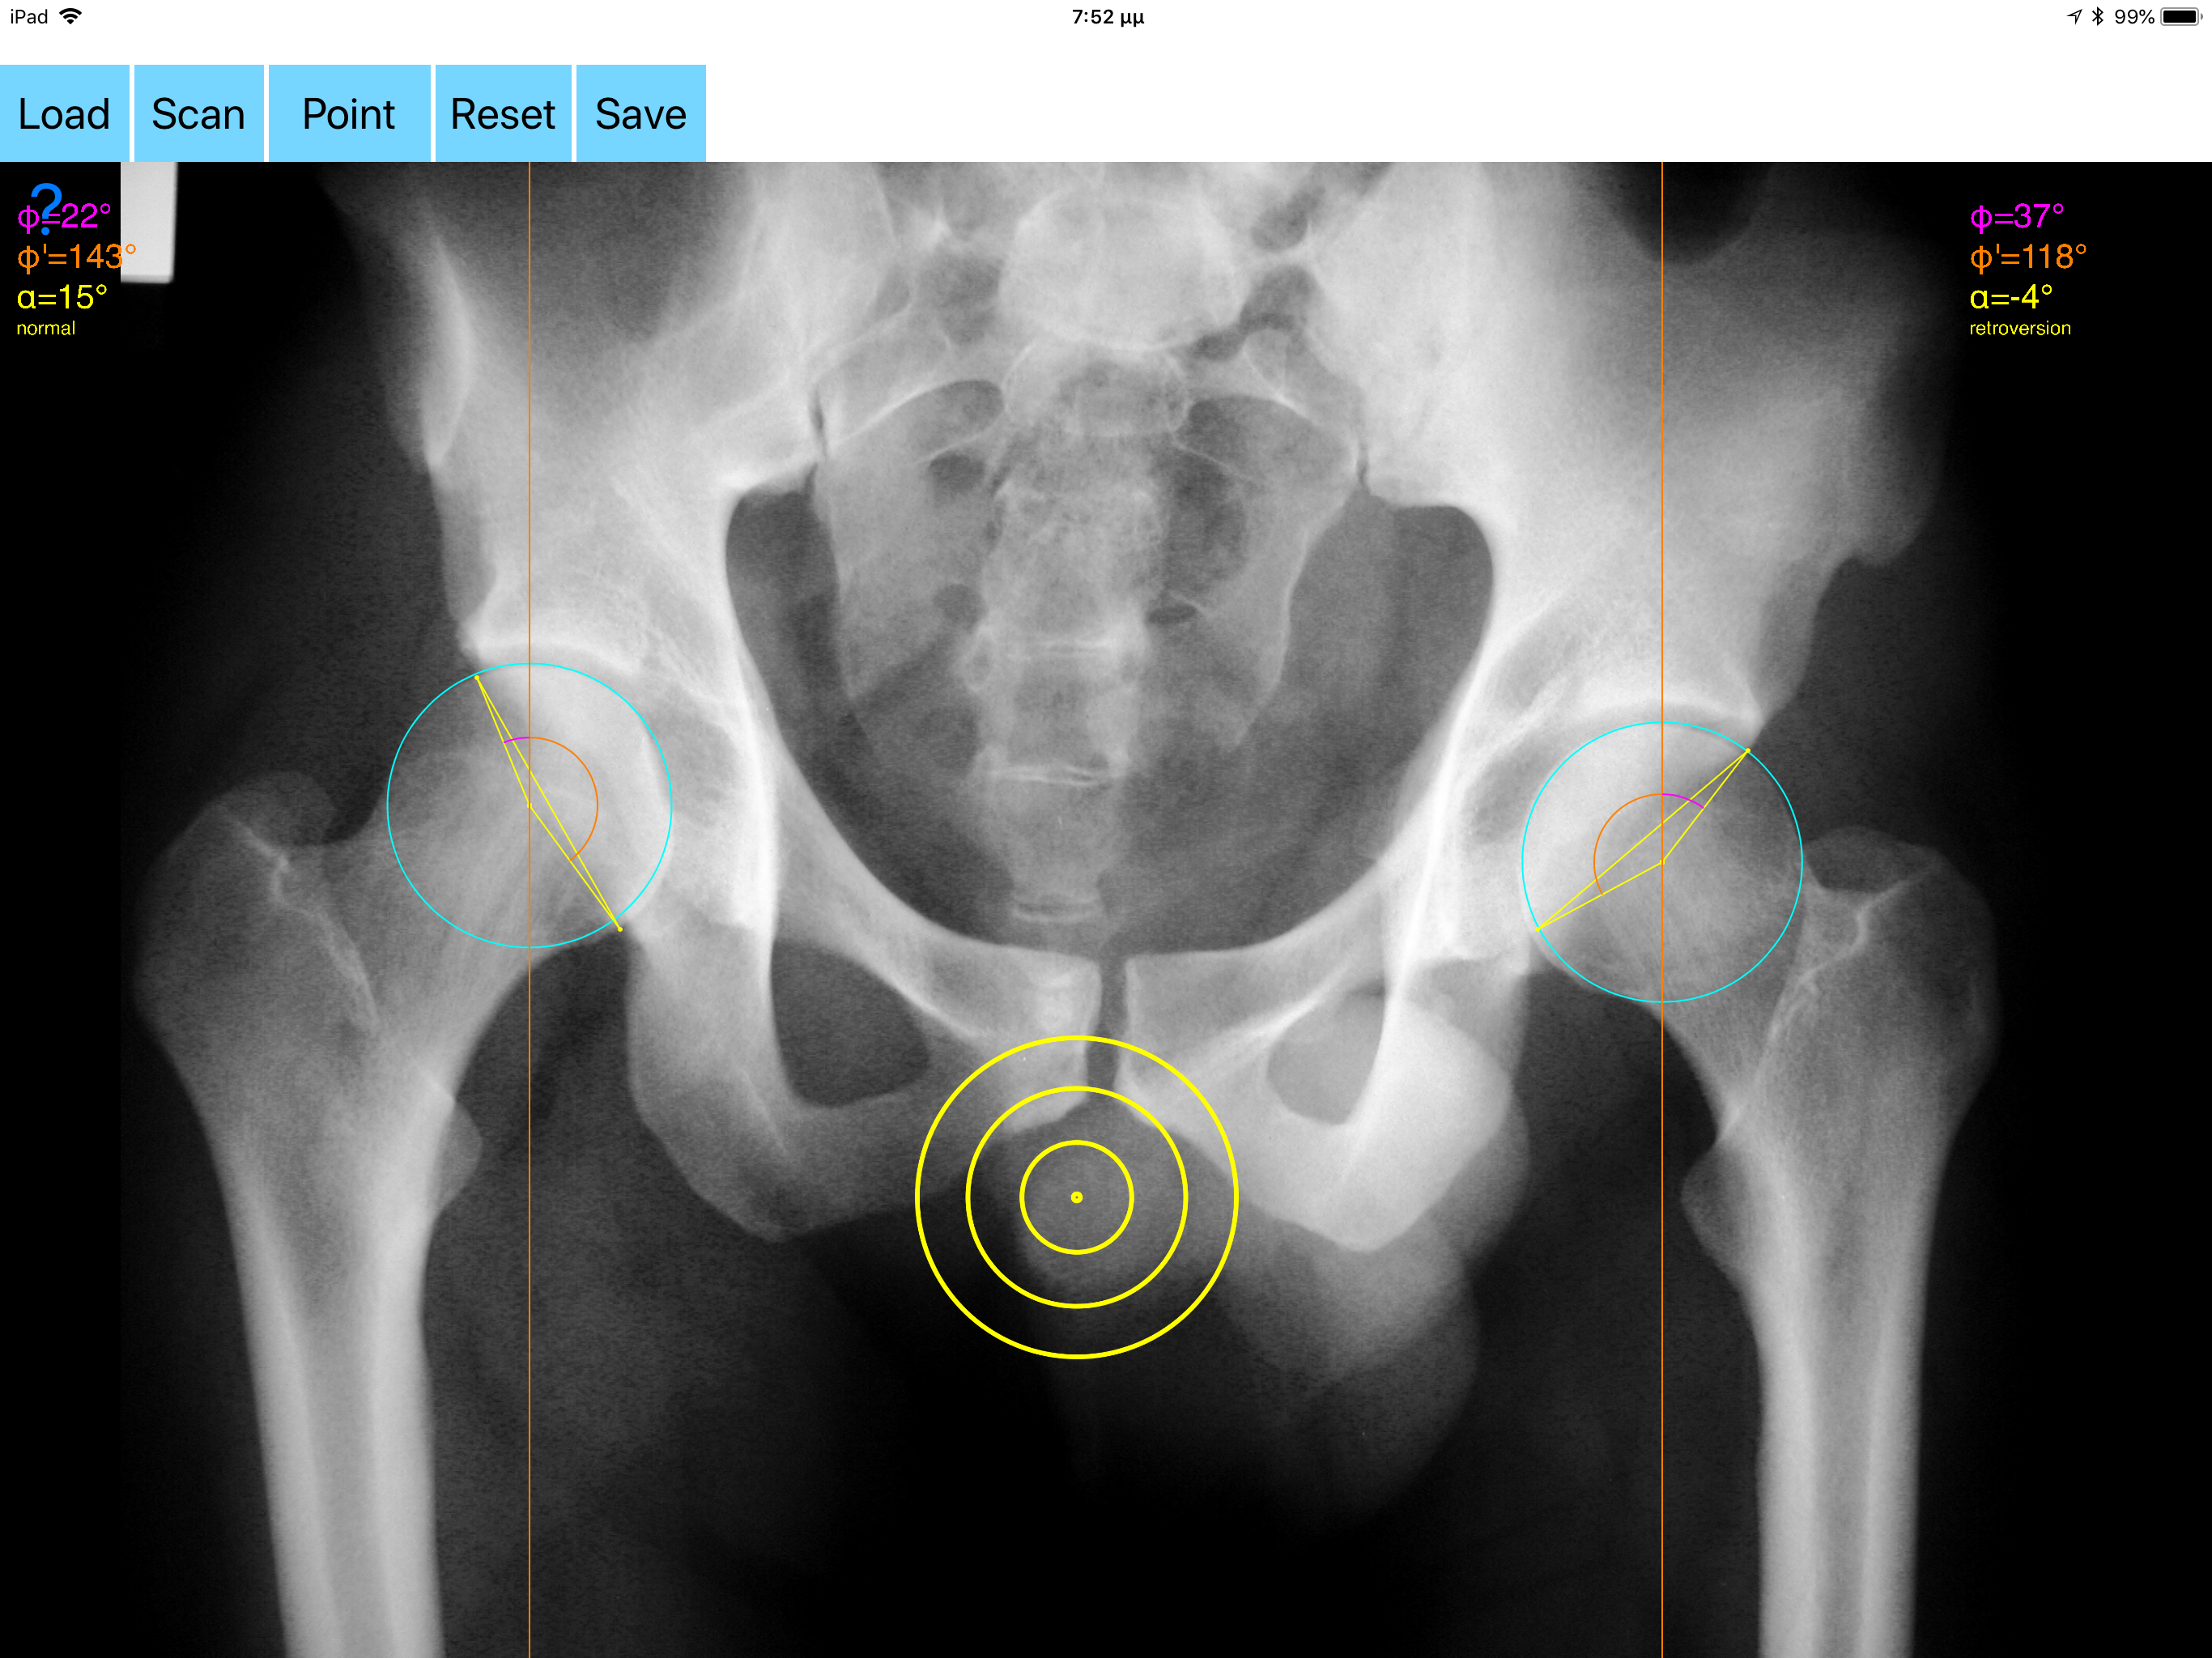

Acetabular version refers to the anteroposterior orientation of the acetabular opening relative to the true horizontal axis of the pelvis. The normal human acetabulum is anteverted in order to allow impingement free range of motion including flexion, adduction, and internal rotation. Abnormal acetabular version has been correlated with pathologic hip conditions including femoroacetabular impingement (FAI) and developmental hip dysplasia.The association between acetabular version and hip pain has been well established in recent years as a source of contributing to early hip osteoarthrosis and labral tears. Recognition and appropriate treatment of abnormal acetabular version is crucial to preventing irreversible damage to the hip Acetabular version is conventionally evaluated on CT scans but excessive radiation doses associated with routine use of computed tomography (CT). An objective radiographic tool which provides measurements comparable in accuracy to CT measurements has been developed by Dr. Hefti (Nomogram).Tedious and time-consuming calculation has to be done in simple X-rays in order to calculate the acetabular anteversion. The primary goal of this App is to help determine radiographic values of acetabular anteversion in a practice in a blink of an eye and avoiding CT scans. The App is medical software aimed for orthopaedic surgeons, providing tools that allow doctors to: -Securely import medical images directly from the camera or stored photos. -By marking certain points in a simple standard AP pelvic radiograph, geometric parameters are being calculated. The App computes the acetabular anteversion based on a pelvic AP radiograph. The angle of anteversion is calculated through the formula according to Heftis nomogram. The acetabular orientation (anteversion/retroversion) is determine by the app by the measurement of the angles between the center of the femoral head and the anterior (φ) and posterior (φ’) acetabular rim. Once you choose correctly the anterior and posterior acetabular rims the app calculates the acetabular anteversion based on nomogram. -The data are printed over to screen so each case can easily assessed -Save the planned images, for later review or consultation. Disclaimer. Regarding its plausibility app offers no diagnosis or treatment. App provide an early indication that further evaluation may be warranted by Speciality Doctor. Explicitly is announced that the apps are not for diagnosis. Clinical judgment and experience are required to properly use the software. App alone do not replace an M.D. or specialist. All information received from the App output must be reviewed before any attempted treatment. The software is not for primary image interpretation. Any influence to the operators in making decisions remains user own responsibility and experience. App does not dispense medical advice. Patient should seek a doctor’s advice in addition using the app and /or before making any medical decisions for themself. Never substitute or replace doctors advice or change treatment modalities based on any measured outcome. App indicated for assisting healthcare professionals for scientific and research reason. Clinical judgment and experience are required to properly use the app and further research and validation is pending in coming future. Reference Friz Hefti, Pediatric Orthopaedics in Practice, Chapter5 , Pelvis hips and thighs 5.3.2.1 Biomechanics of the hip-Book. Springer